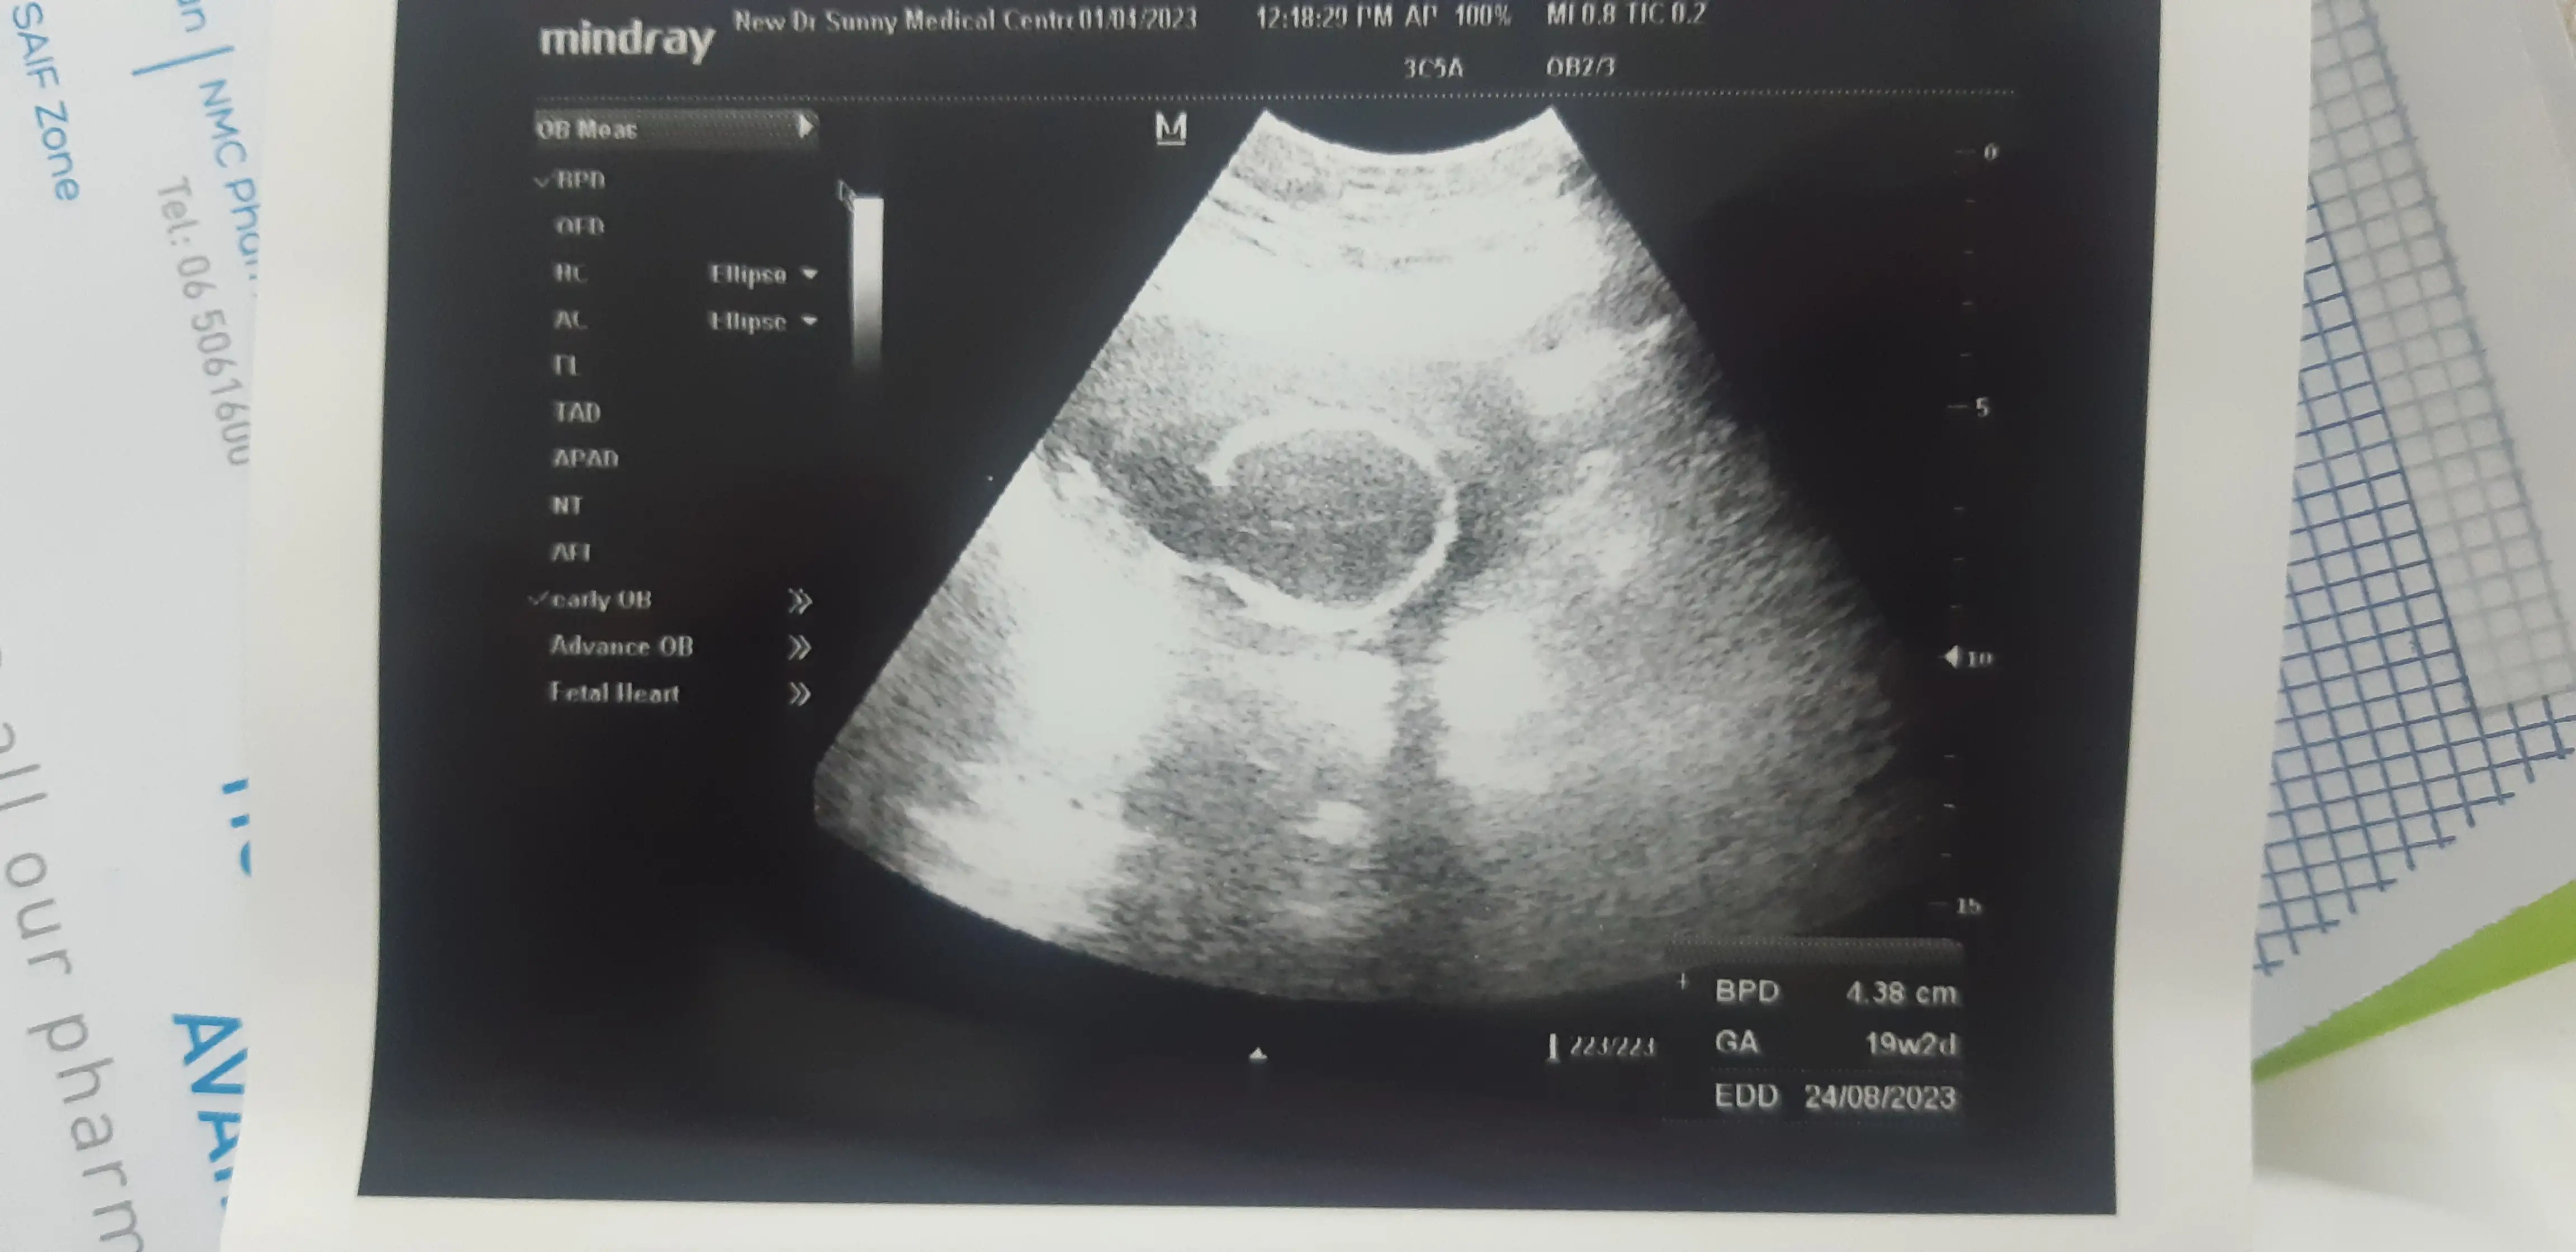

Q: Hi I'm in dubai jo dr se mera treatment chal raha tha woh India leave par chali gai. Aaj dusri dr ke pass visit kiye woh bohat khadus thi kuch update hi nahi di thik se. Sirf lecture de rahi thi yaha q paise laga rahi ho India jao n all. Please mujhe batao report thik haina?